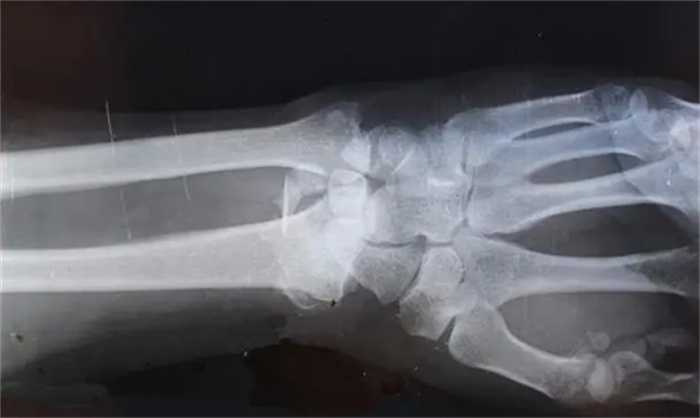

在1994年约翰就发生了一起车祸,当时他被车撞飞了好几米远,这样的撞击足以让一个普通人的骨骼碎裂大半,但是约翰当时只是感觉身体有些疼痛,并且在送往医院拍摄了X光片之后,一生惊讶的发现,约翰的骨骼并没有任何一处碎裂,甚至连一个骨折都没有找到,这就让医生十分惊奇,难道说约翰在面对货的时候运气好,刚好借助了巧力。

不过很快医生就发现了问题所在,原来是约翰的骨骼密度是和葡萄人相比非常的高,大概是正常人的八倍左右,也就是说他的骨骼坚硬程度最起码是正常人的八倍以上,所谓的骨骼密度说的就是在人体骨头当中矿物质的质量,往往骨骼的矿物质量越多。就可以说明骨骼更加坚硬,另外还有一点很让人惊讶,就是他这么高的骨头密度并没有对他的身体造成其他的影响。反而有着非常强大的抗击大能力以及强大的恢复能力。